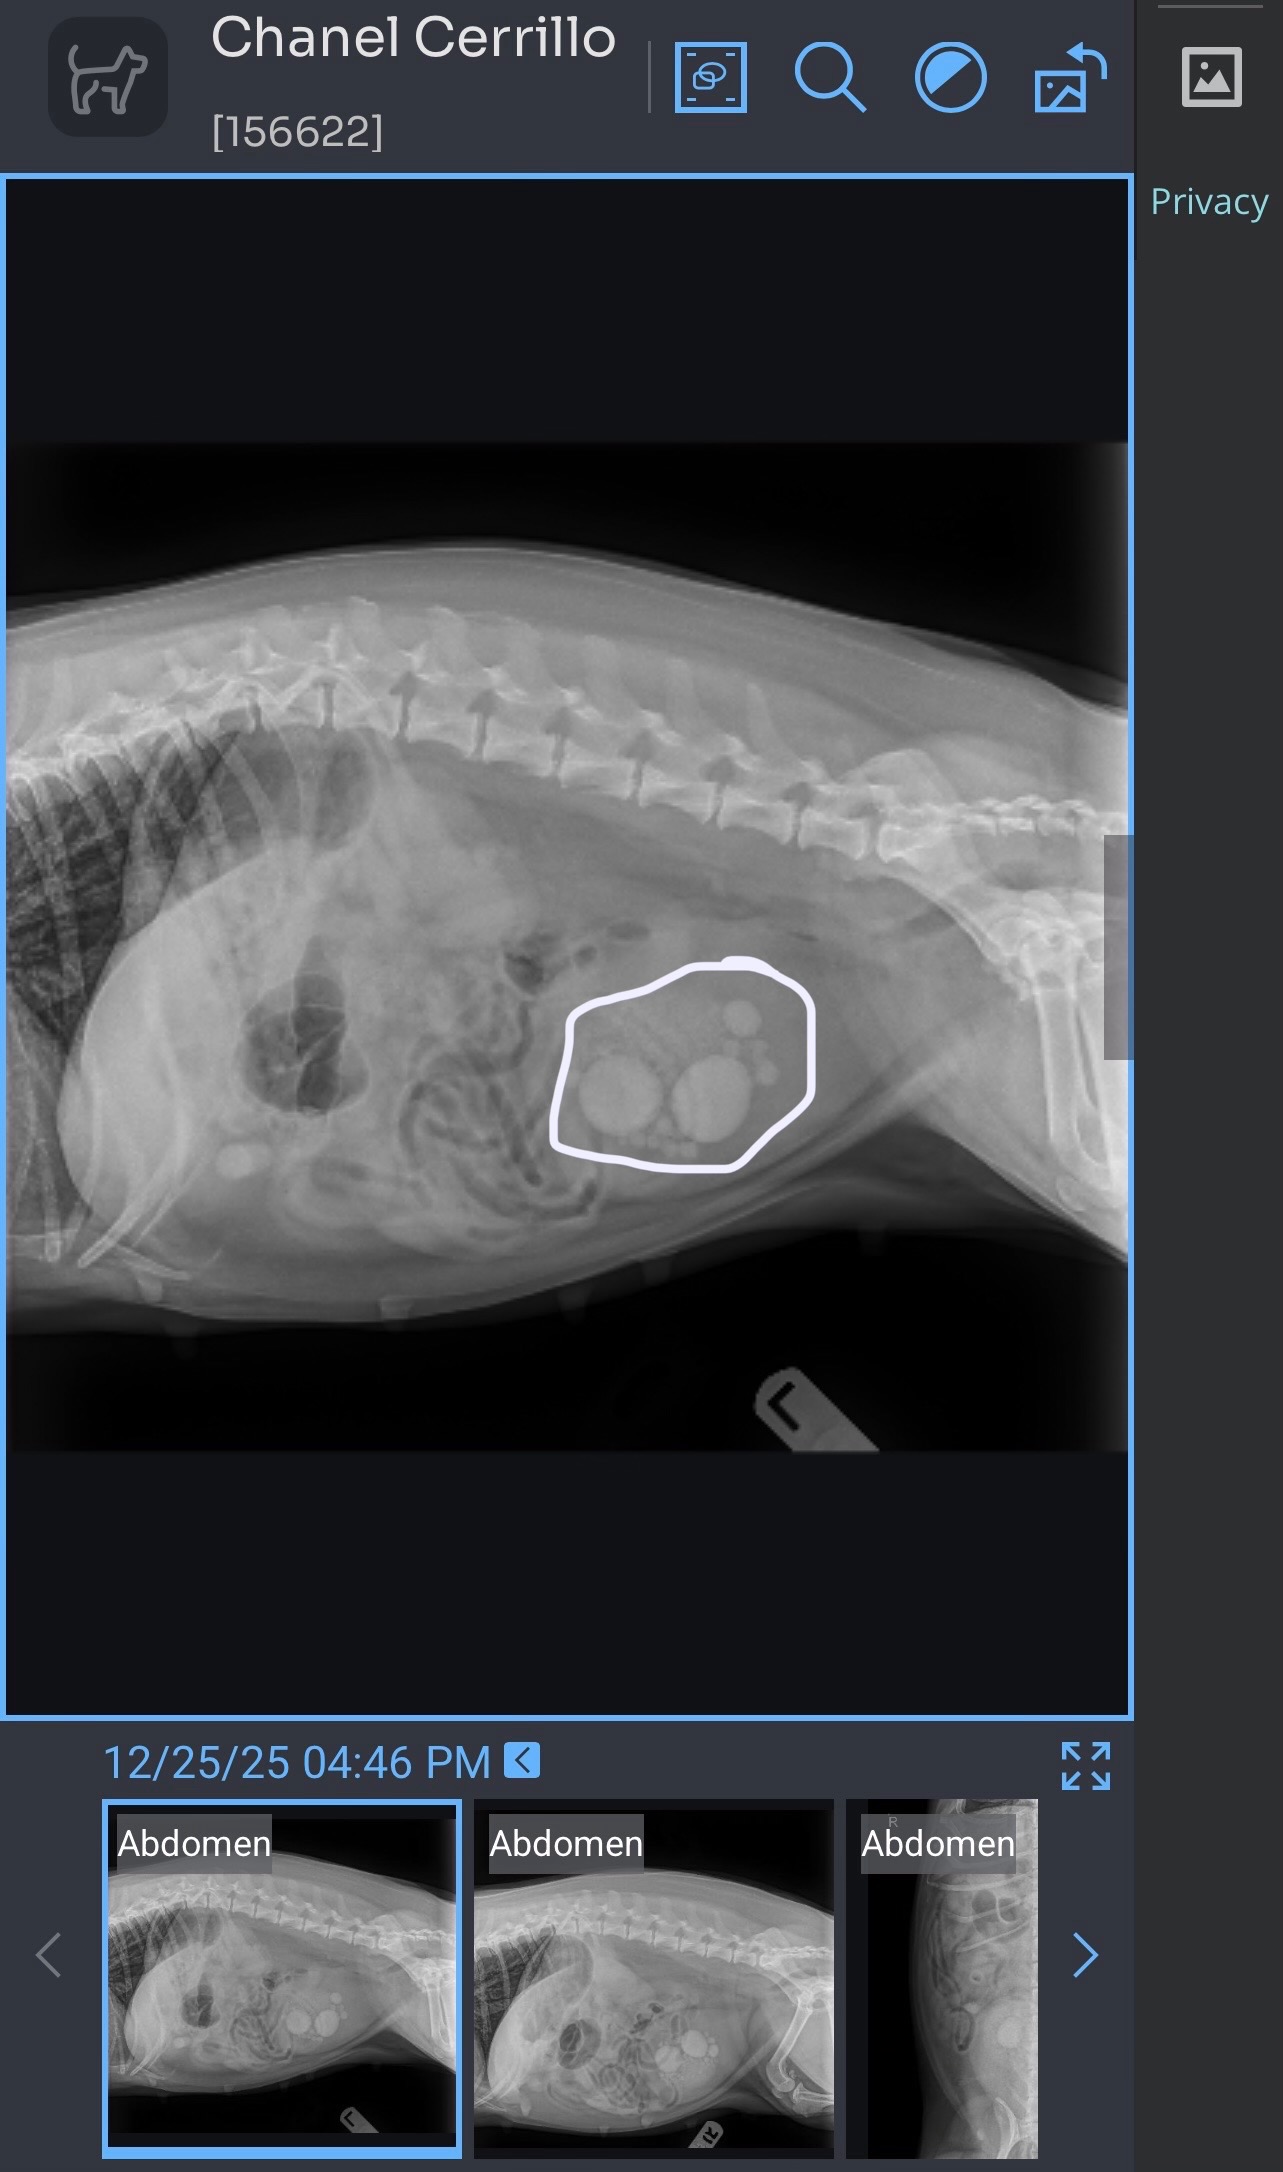

Last night was one of the scariest nights I’ve had as a pet parent. My dog Chanel suddenly needed to go to the ER, and after a series of blood tests and exams, the vets discovered she has stones in her bladder. The only way to help her feel better and get back to her happy, loving self is to have surgery to remove the stones. As you can imagine, this news was overwhelming and unexpected, and I want to do everything I can to make sure Chanel gets the care she needs.